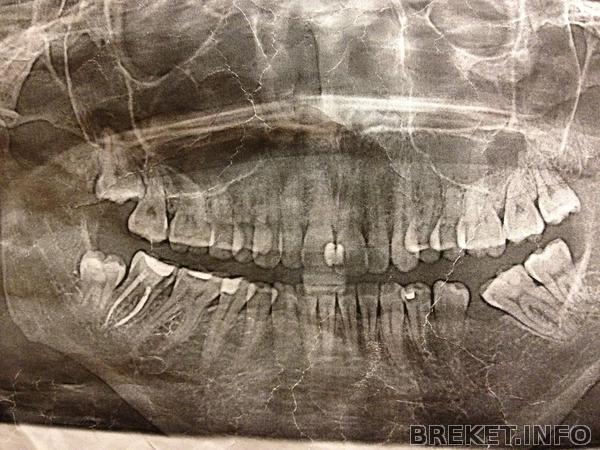

Правда, еще неделя до 5 месяцев, но я меряю походами к ортофее, а я к ней уже сходила, в общем, примерно 5 месяцев. Дугу мне пока не меняют, пообещали через 2 месяца обе дуги пожестче. А пока фея ушла в отпуск. Есть небольшие результаты, и я решила сделать коллаж..вот

низ у меня тоже потихоньку ровняется, как и в случае с верхом, левая сторона поддается быстрее)))качество плохое, к сожалению, ну это потому что мне неудобно фотографировать нижние зубы

но в общем надеюсь понять можно: